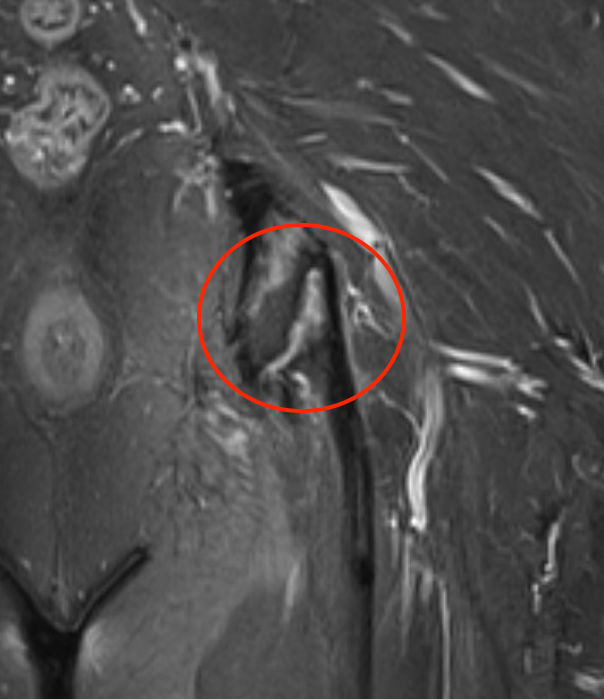

MRI

Peritendinous edema / low grade partial tears / tendinopathy

High grade partial tears

- identify high grade partial tear

- peel off

- debride and repair

Elevate high grade tear with Cobb, exposing bare ischial tuberosity (*)